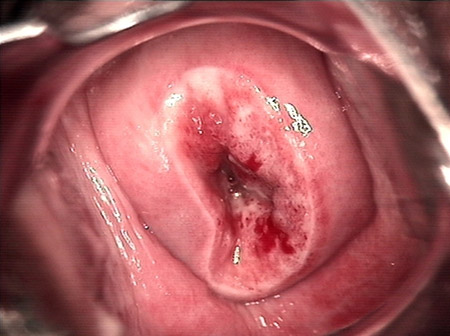

婦科leep錐切手術(shù) CIN2-3

CIN 2-3

CIN 2-3 碘著色后